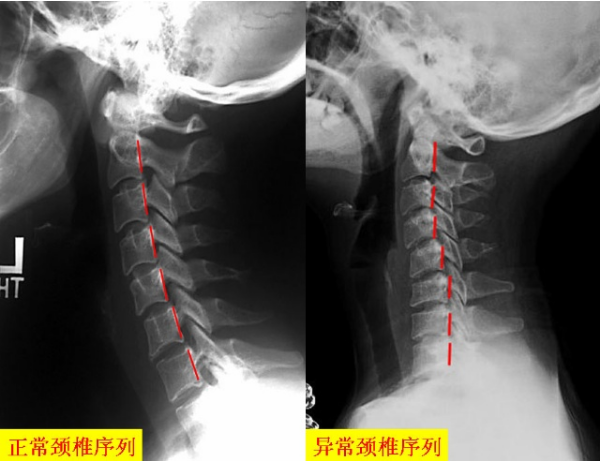

骨質(zhì)增生癥是一種退行性病變的骨骼特征病,也是中老年人的常見(jiàn)病,多發(fā)病,隨著我國(guó)老齡化趨勢(shì)的加快骨質(zhì)增生以及成為微信到老人的健康疾病,通過(guò)研究表示,骨質(zhì)增生以及越來(lái)越年輕化。頸椎骨質(zhì)增生會(huì)引起頭痛,頭暈,下肢手足麻木,輕會(huì)影響工作,重者會(huì)出現(xiàn)半身癱瘓的現(xiàn)象。生活無(wú)法自理,骨質(zhì)增生應(yīng)該提前做好預(yù)防,保健,改善和康復(fù)的工作。怎么治呢?(文章整理小編微信:wangjiuzheng88)

2、姿勢(shì)不良:如長(zhǎng)期伏案工作者、睡眠姿勢(shì)不良、枕頭不合適者頸椎骨質(zhì)增生的發(fā)病率特別高,由于頸椎的部分肌肉呈持續(xù)緊張狀態(tài),久之這些肌肉發(fā)生靜力性損傷,進(jìn)而是頸椎發(fā)生退行性改變而引起骨質(zhì)增生。也與頸椎關(guān)節(jié)長(zhǎng)期受力不均,使壓力(應(yīng)力)集中于關(guān)節(jié)內(nèi)的某處造成應(yīng)力過(guò)度而損傷關(guān)節(jié)。